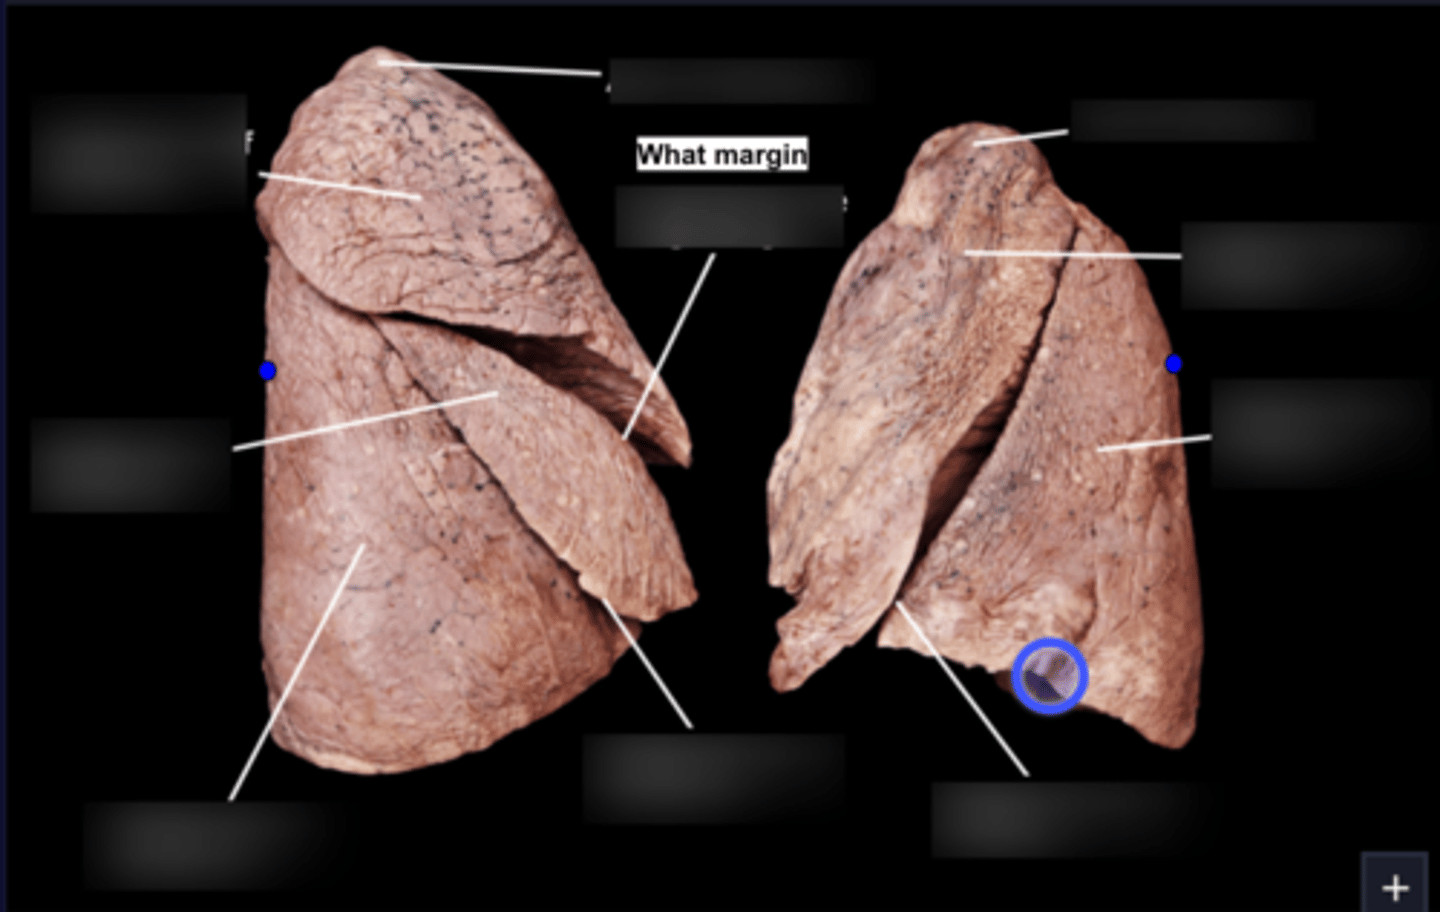

Superior lobe of right lung

Middle lobe of right lung

Inferior lobe of right lung

Superior lobe of left lung

Inferior lobe of left lung

Lingula

Apex

Base/Diaphragmatic Surface

Costal Surface

Mediastinal Surface

Anterior Margin

Posterior Margin

Visceral Plurae